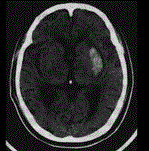

问题 患者,68岁,有高血压病史5年,突发头痛2天入院,行头颅CT出现如图所示脑出血,该病灶最可能是下列哪条破裂引起 ( )

选项 A、脉络膜前动脉 B、豆纹动脉 C、纹状体内侧动脉 D、大脑中动脉主干 E、丘脑穿通动脉

答案 B